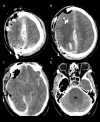

BACKGROUND Decompressive craniectomy is a common life-saving intervention in the setting of elevated intracranial pressure. Cranioplasty restores the calvarium and intracranial physiology once swelling recedes. Cranioplasty is often thought of as a low-risk intervention. However, numerous reports indicate that malignant cerebral edema (MCE) is an often-fatal complication of an otherwise uneventful cranioplasty. A careful review of the literature is needed to better understand this devastating condition. CASE REPORT A 41-year-old man presented after suffering a gunshot wound to the right frontal lobe. Upon initial evaluation, the patient had grossly visible brain matter, left-sided hemiparesis with a Glascow Coma Score (GCS) of 11, and vital signs concerning for elevated intracranial pressure. Computed tomography (CT) showed right-sided intraparenchymal and subarachnoid hemorrhage with a 5 mm leftward midline shift. The patient was taken to the operating room (OR) for right fronto-parietal craniectomy. Over the next 3 months, he recovered steadily and underwent PEEK cranioplasty on post-operative day 83. Pre-operative CT showed sunken skin flap syndrome with an 8-mm midline shift. Following an uneventful cranioplasty, he failed to regain consciousness. Examination revealed absent brainstem reflexes. CT showed global diffuse cerebral edema. The patient was declared brain dead. CONCLUSIONS Continued research is needed to better understand the pathophysiology of malignant cerebral edema so that future incidences may be prevented. A combination of negative-pressure suction drainage, sunken skin flap syndrome, and delayed time to cranioplasty likely play a significant role in the evolution of MCE. We urge neurosurgeons to consider the likelihood of MCE and adapt surgical planning accordingly.